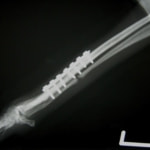

トイプードル 右遠位橈尺骨短斜骨折のALPSによる内固定